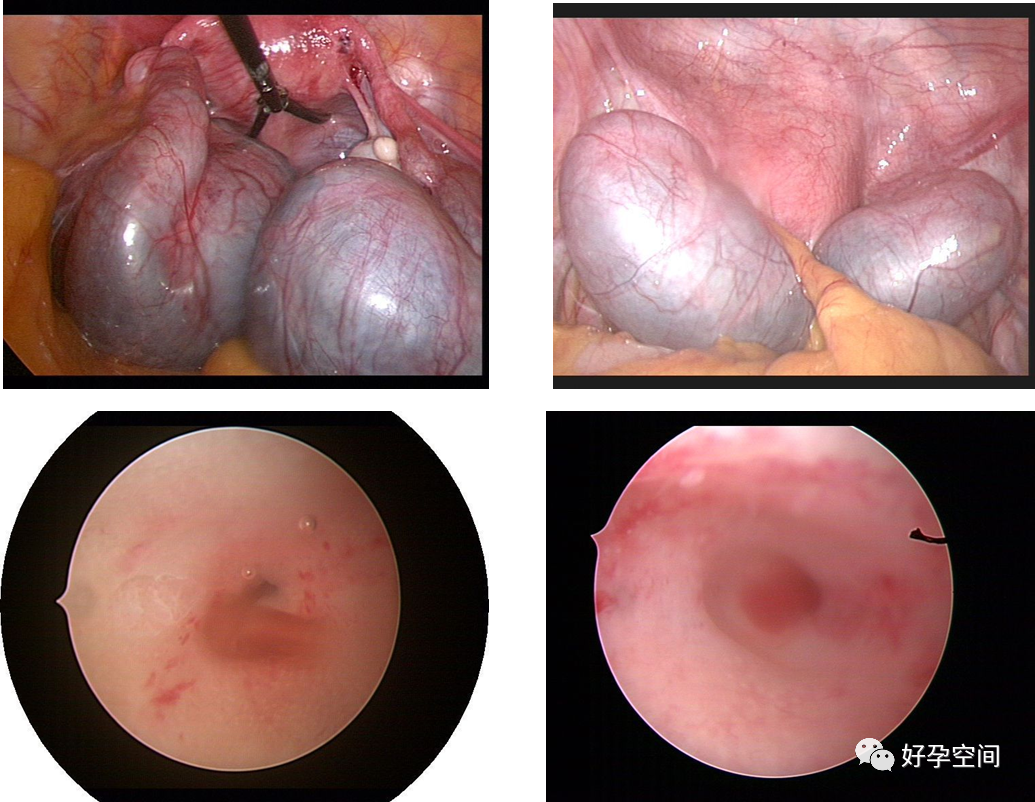

5、阴道异物、阴道纵膈、宫腔异物、宫颈管纳氏囊肿穿刺或开窗、女性尿道检查,宫腔镜膀胱灌注、膀胱异物取出、膀胱血块清除、膀胱出血点电凝止血。

幼女检查阴道,排除阴道异物

切除阴道纵膈

宫腔缝线异物

宫颈纳氏囊肿单极电针穿刺

宫颈纳氏囊肿开窗

尿道口肉阜切除,检查尿道及膀胱

气囊尿管爆裂,橡皮片遗留膀胱

取卵损伤膀胱,清除膀胱内血块,电凝止血

输尿管插管